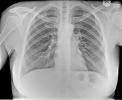

La sarcoidosi polmonare è una malattia rara di tipo infiammatorio e cronico che colpisce i polmoni. La sarcoidosi di per sé è un'infiammazione che può colpire quasi qualsiasi organo, ma la sarcoidosi polmonare è la forma più comune, con oltre il novanta per cento dei casi.

Tra le malattie polmonari, una delle più comuni è senza dubbio l'enfisema, una patologia tipica dei polmoni che si distingue per un tipo di alterazione anatomica caratterizzata da ingrossamento degli spazi aerei in prossimità dei brochioli polmonari con disgregazione delle pareti alveolari, senza formazione di fibrosi.